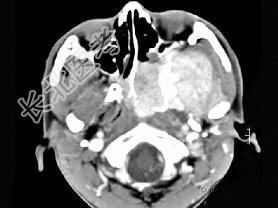

- 单项选择题男性,19岁, 左侧鼻腔反复出血一年余,CT、MRI扫描如图所示, 请选择最可能诊断 ( )

C、鼻咽部青年纤维血管瘤